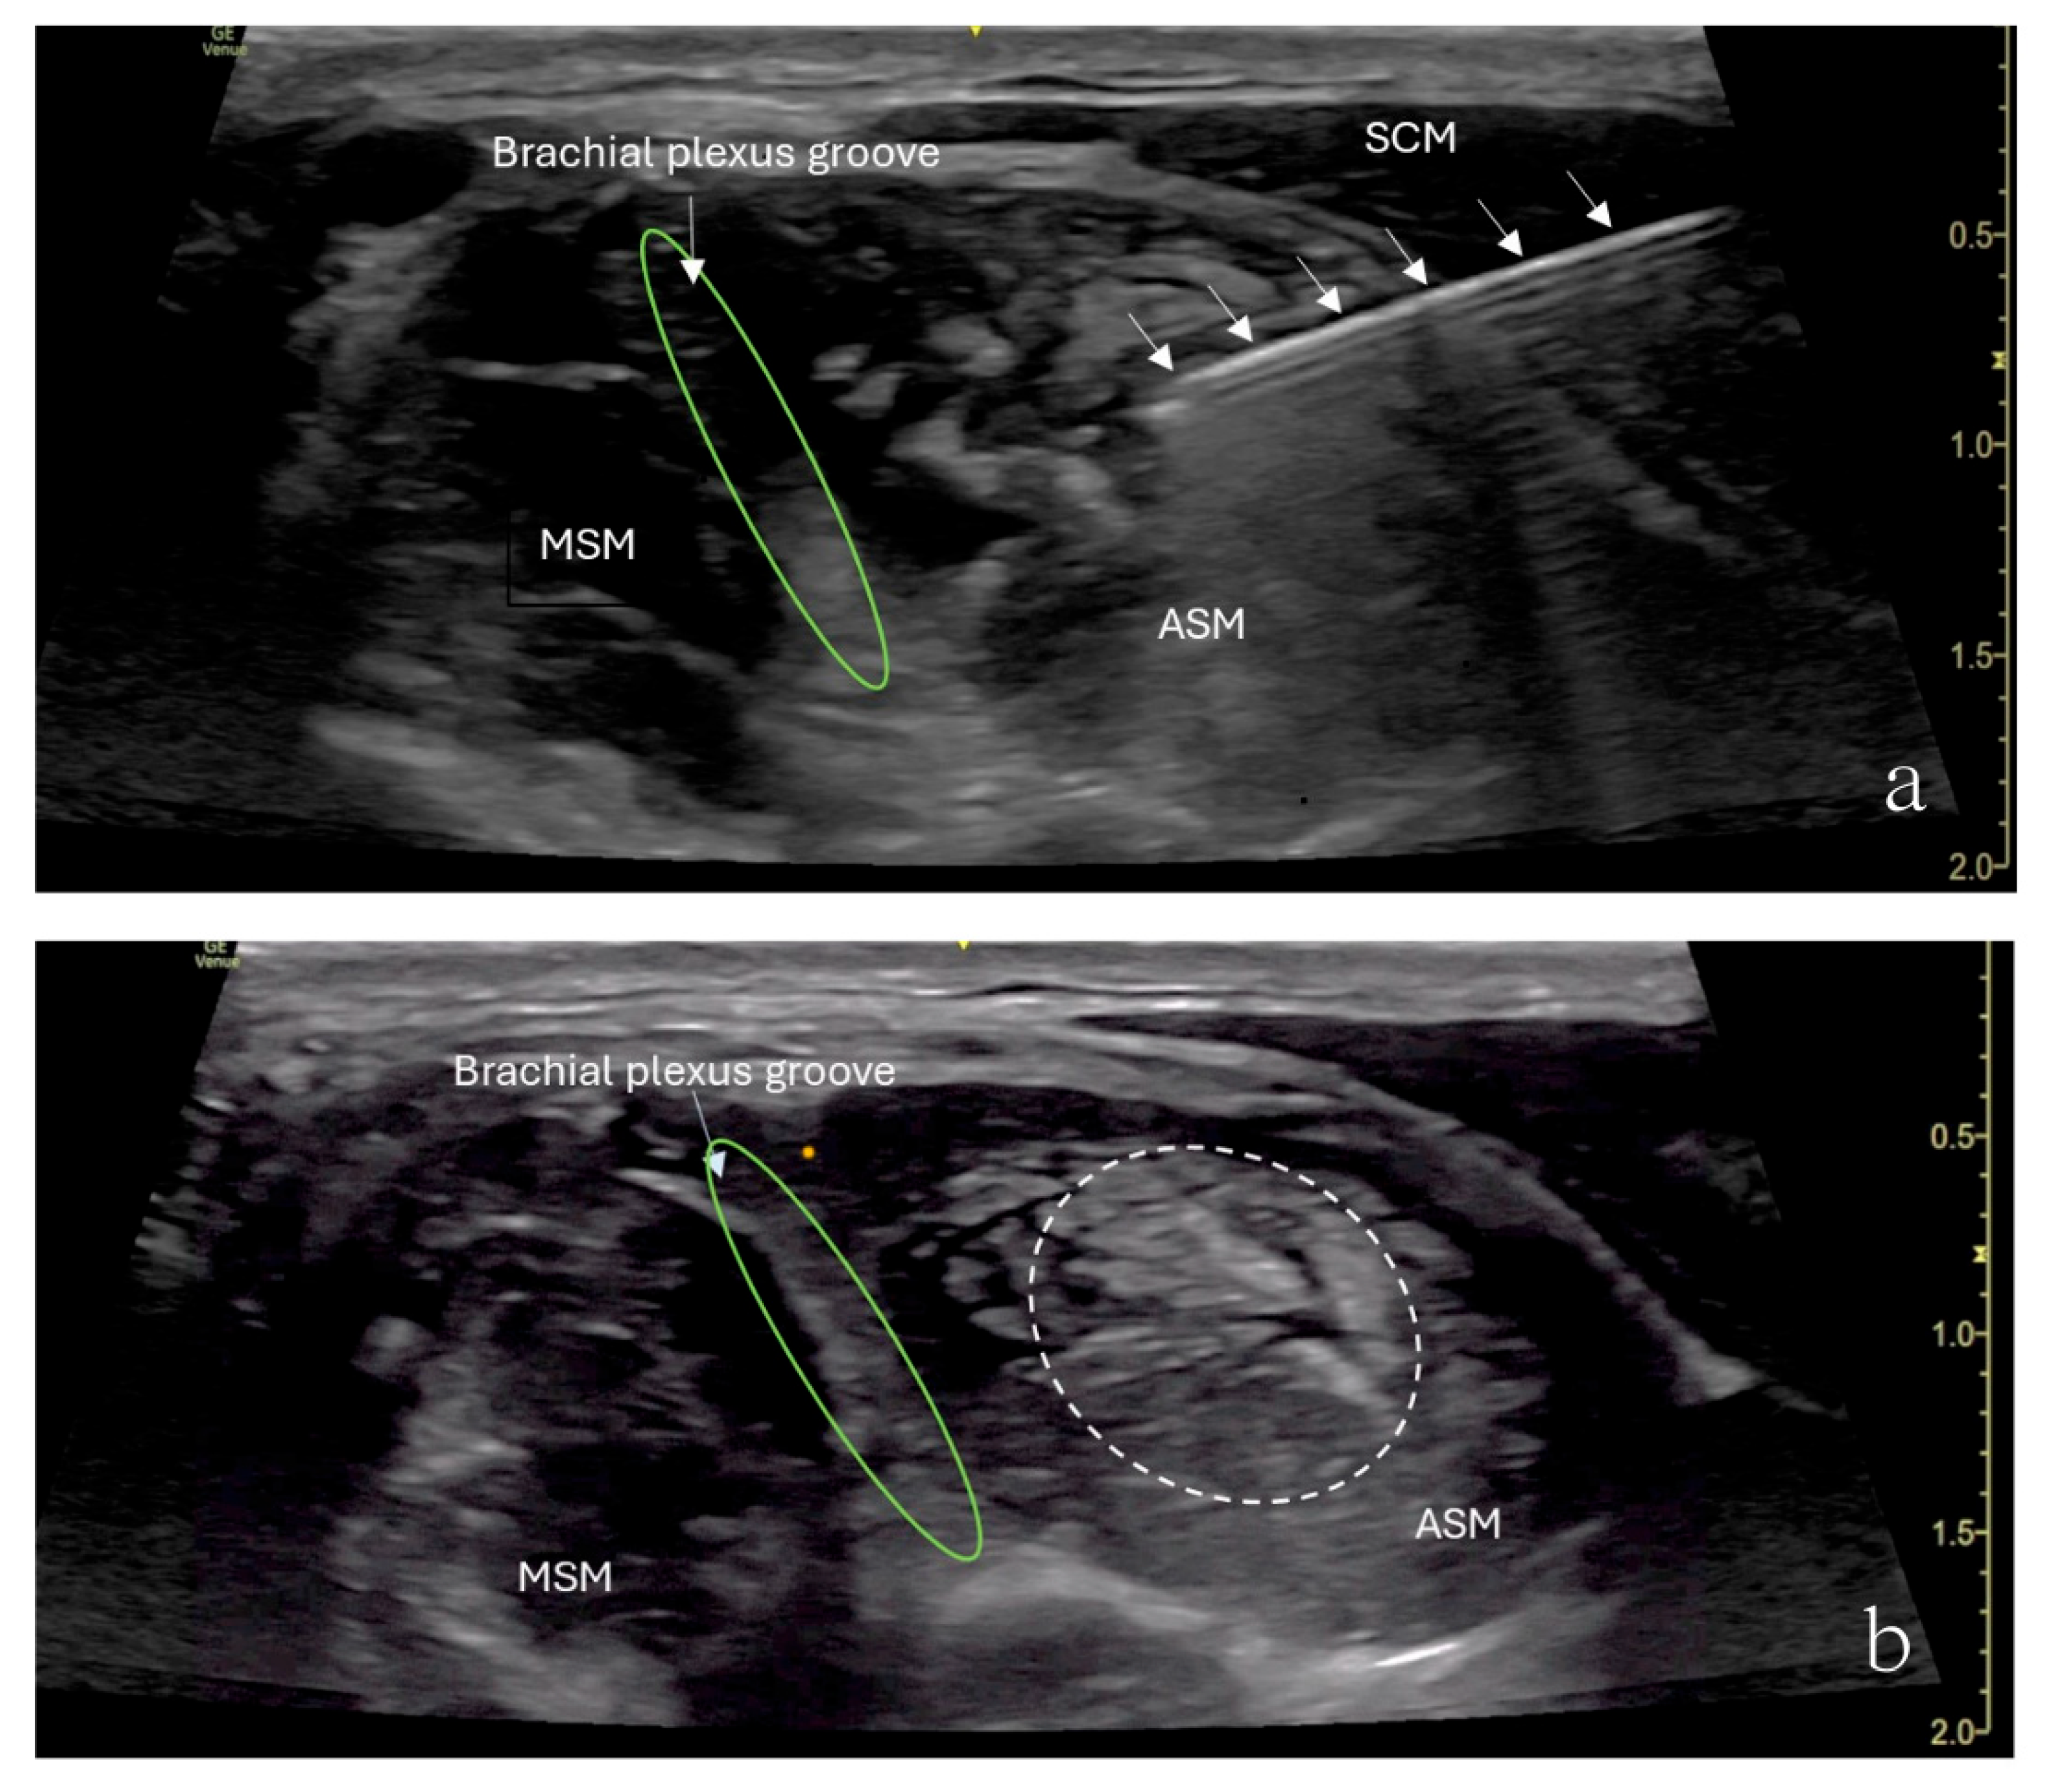

The patient underwent an ultrasound-guided right anterior scalene muscle block under minimal sedation. A high-frequency linear probe was used to identify the anterior scalene muscle (Figure 1). After sterile preparation, a 22-gauge, 50 mm Sono-TAP needle (PAJUNK®, Geisingen, Baden-Württemberg, Germany), using an in-plane technique, was advanced from the posterior aspect of the neck anteriorly and was inserted into the middle of the anterior scalene muscle. After negative aspiration of blood, 5 mL of 0.5% ropivacaine was slowly injected in increments. An increased muscle size was observed with no medication extravasation to the brachial plexus divisions (Figure 1). After the procedure, the patient’s preexisting numbness disappeared, her weakness in her right shoulder disappeared, and her hand strength improved. However, she reported shoulder heaviness though she had a full range of motion.

Figure 1.

Ultrasound image showing an anterior scalene muscle block in a 12-year-old girl. (a) SCM—sternocleidomastoid muscle, MSM—middle scalene muscle, ASM—anterior scalene muscle, IJV—internal jugular vein. The interscalene nerve roots (C5,6,7) are highlighted with a green circle. (b) The needle (arrows) is inserted into the middle of the anterior scalene muscle (ASM) from the posterior aspect of the neck anteriorly, with local anesthetic spreading within the muscle (dashed line). The brachial plexus groove lies between the ASM and MSM.